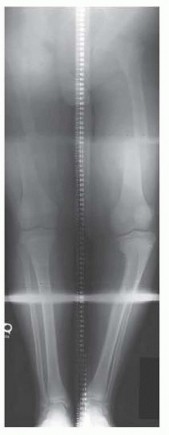

Guided Growth to Correct Limb Deformity DEFINITION The anatomic axis is the mid-diaphyseal line of a bone. Th…

Surgical Management of Blount Disease DEFINITION Blount disease, also known as idiopathic tibia vara and oste…